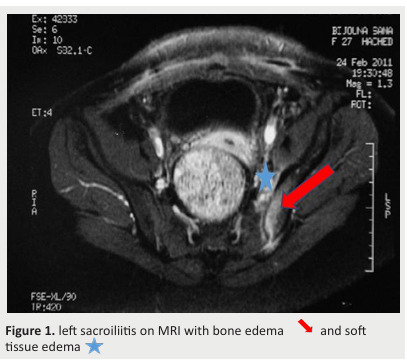

Introduction-Aim: Postpartum septic osteoarthritis is a rare but serious condition often misdiagnosed due to overlap with common postpartum symptoms like pelvic pain and joint stiffness. This case series aims to describe the clinical, bacteriological, and radiological characteristics of postpartum septic osteoarthritis, as well as the treatment approaches and patient outcomes. Methods: A retrospective case series was conducted at Farhat Hached University Hospital, from 2006 to 2022, involving patients with confirmed postpartum septic osteoarthritis. Clinical data, laboratory findings, imaging results, treatments, and outcomes were analyzed Results: The mean age of the seven patients was 31.4 years. All patients presented with joint pain, with fever and functional impairment where each was observed in 85.7% of cases. The average diagnostic delay was 17 days. MRI findings revealed bone marrow edema in all patients, Abscesses in 28.5% of cases, periarticular soft tissue edema, and intra-articular effusions in 71.4% of cases. The pubic symphysis was the most commonly affected site (57.1%), followed by the sacroiliac joints (28.6%). Only one pathogen, Streptococcus pyogenes, was isolated. Nearly all patients received dual antibiotic therapy for an average duration of 4 to 6 weeks. Satisfactory clinical progress without sequelae was noted and maintained after an average follow-up of 5 to 6 months. .Conclusion: Our results revealed that postpartum septic osteoarthritis requires prompt diagnosis and early treatment to prevent severe complications. MRI plays a critical role in early detection, while timely antibiotic therapy leads to favorable long-term outcomes.